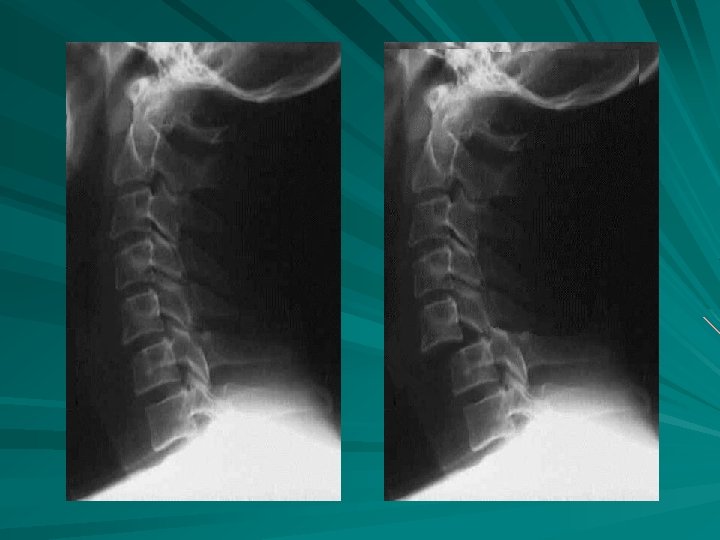

X-TABLE LATERALS CERVICAL SPINE

Dislocation of the C 3 and C 4 articular processes Note that C 7 is not well demonstrated

Some studies of spinal trauma have recorded a missed injury rate as high as 33%.